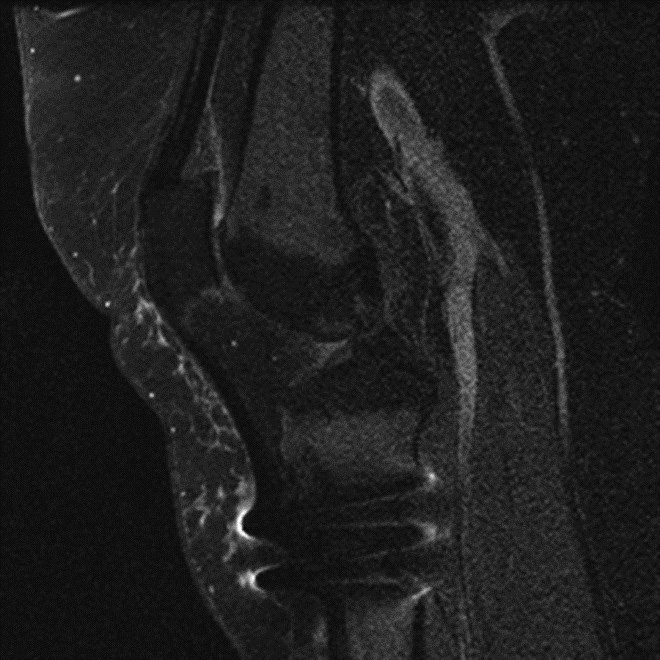

| Inversion Recovery Imaging. (B) Axial STIR MR image in the same patient reveals fluid-signal pseudotumor (arrow) adjacent to the left greater trochanter, which was obscured on prior examination. |

On MRI, pseudotumors will appear as solid, cystic or mixed masses adjacent to and possibly communicating with the hip joint with potential intralesional or peripheral low T2 signal, reflecting metal deposition (Figure 24) (Chen, 2011). Solid lesions more commonly occur anteriorly, usually within the psoas muscle and may extend proximally into the pelvis (Figure 25) (Ostlere, 2011). Predominantly cystic lesions typically arise from the posterior joint space and may or may not demonstrate wall-thickening. Lateral lesions usually involve the trochanteric bursa and often communicate with the joint space. Differentiation of cystic and solid lesions may be difficult and the use of post-contrast imaging is not helpful for lesion detection, particularly due to surrounding metallic artifact. There may be involvement of the adjacent osseous structures with associated erosions, as well as the soft tissues, particularly the gluteal tendon attachments with resulting tendon disruption and muscle atrophy (Figure 26) (Anderson, 2011). In rare cases, the reactive process may involve pelvic or lower extremity arteries or the femoral nerve, particularly when occurring anteriorly (Clayton, 2008; Chen, 2011). At present, there is no established pathway for the management of metal-on-metal pseudotumor patients, and follow-up imaging may be performed to assess lesion progression before proceeding to revision, especially with small lesions or minor symptoms.